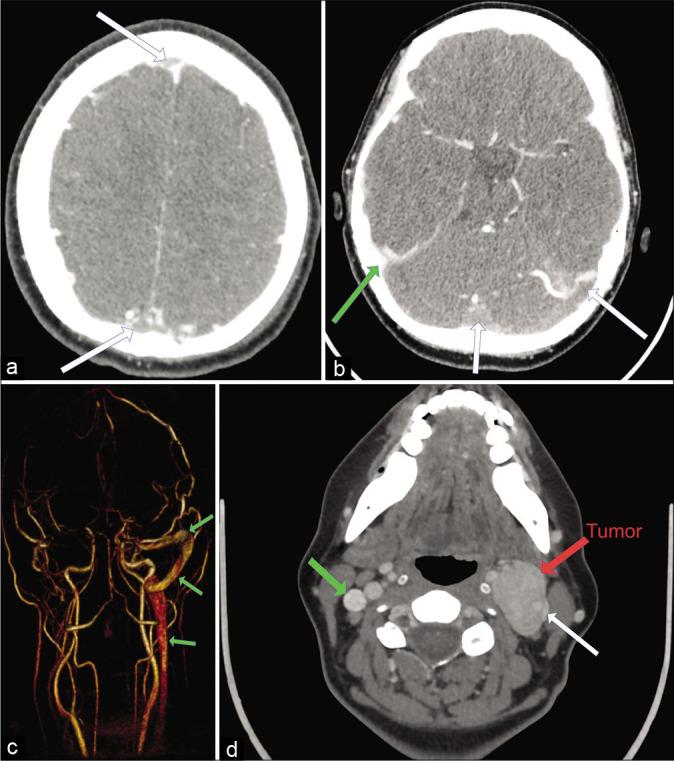

A 38-year-old woman, with no medical history, was admitted in the emergency unit with acute onset of headache, dizziness, and vomiting. On the diagnostic imaging studies (CT venography and MRI) a near total occlusion of all cerebral venous sinuses and a large CBT (Shambin Type II) were diagnosed. Initially, the patient was treated with anticoagulants for the thrombosis and with lumbo-peritoneal (LP) shunt for the management of pseudotumor cerebri. At a second stage, after resolution of the cerebral sinus thrombosis, the CBT was completely resected under electrophysiological monitoring, without preoperative embolization. At 1-year follow-up, the patient is neurologically intact with functioning LP shunt, patent cerebral venous sinuses, without tumor recurrence.

一名38岁无病史女性因突发头痛、头晕和呕吐入住急诊科。经诊断性影像学检查(CT静脉造影和MRI),诊断为所有脑静脉窦几乎完全闭塞以及一个大型CBT(Shambin II型)。最初,患者接受抗凝治疗以处理血栓形成,并采用腰大池-腹腔(LP)分流术治疗假性脑瘤。在第二阶段,脑静脉窦血栓溶解后,在电生理监测下完全切除CBT,未进行术前栓塞。随访1年,患者神经功能完好,LP分流管功能正常,脑静脉窦通畅,无肿瘤复发。